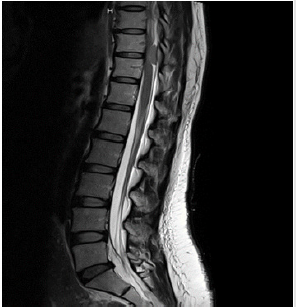

A 37 years old female with 38 weeks of gestation was planned for cesarean section due to breech presentation. The patient was healthy and was not taking any medication. The vital signs, general physical examinations and routine investigations were unremarkable. Spinal anesthesia was performed with aseptic technique at the L3-4 interspace in paramedian approach using a 27G Quincke spinal needle in a single attempt. After confirming entry by free flow of clear cerebrospinal fluid (CSF), 10mg of 0.5% hyperbaric bupivacaine with 0.2mg of morphine was given in a total volume of 2.2 ml. The patient then developed a sensory blockade up to T4 dermatomal level. Intraoperative course was uneventful and all the vital parameters were maintained within normal range. Eight hours after the surgery, the patient still had lower extremities weakness. She had no fever or back pain. Neurologic examinations revealed loss of sensation below L1 dermatome and decreased motor strength of both lower extremities, according to Medical Research Council grading, quantified as followed: bilateral hip flexion II/V; bilateral knee extension II/V; bilateral foot dorsiflexion IV/V; and bilateral plantar flexion IV/V. Both lower extremities showed increased muscle tone and prepatellar reflexes. Rectal and sphincter tone were decreased. Besides that, the patient also mentioned that 2 weeks prior to admission she started feeling numbness in legs but did not recognize that as a problem. An urgent magnetic resonance imaging (MRI) of thoracolumbar spine shows dural-based mass at posterior wall of thecal sac at the T10-T11 vertebral level with spinal cord compression (Figure 1). Microscopic decompressive laminotomy with tumor removal was operated on the next day. After surgery, the patient’s symptoms began to resolve, and she was able to walk with assistance. Pathological study of the tissue showing atypical meningioma (WHO grade II) was reported. Four months later, she was fully recovered and repeated MRI thoracolumbar spine showed no residual tumor (Figure 2).

Figure 1: Magnetic resonance imaging of spine showing dural-based mass at posterior wall of thecal sac at the T10-T11 vertebral, measured 0.9x1.0x2.0cm. in dimension. Mass effect with spinal stenosis and spinal cord compression.